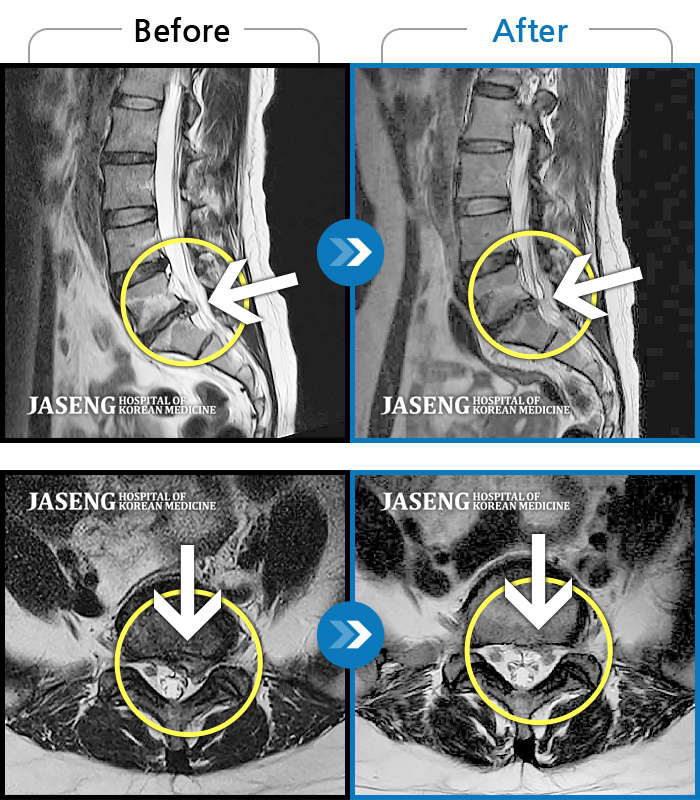

[뱸] 19.11.28~25.05.06

ȯںп Ǹ ǿ ԿǾ, ο ġ ۿ Ƿ ġḦ Ͻñ ٶϴ.